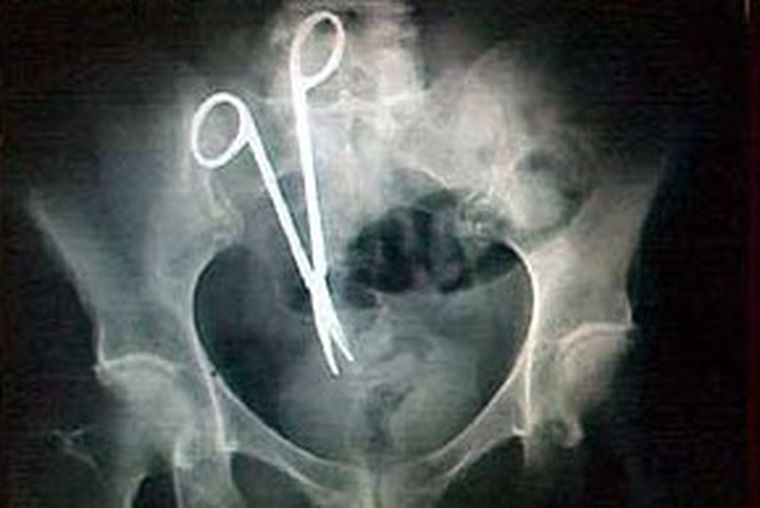

En Argentina, las demandas por mala praxis médica suman 1.260 millones de dólares

Las demandas judiciales en curso por mala praxis médica en Argentina suman reclamos económicos por unos 5.000 millones de pesos (unos 1.260 millones de dólares), según un informe presentado hoy en un congreso del sector sanitario.

Según la entidad, las demandas y amparos judiciales contra el sistema sanitario argentino crecen a un ritmo del 10 por ciento anual, aunque sólo tres de cada diez recursos legales presentados prospera y el resto es desestimado por los jueces.

En el marco del XIII Congreso Argentino de Salud que se realiza en la ciudad argentina de Mendoza (oeste) organizado por la ACAMI, el titular de la Corte Suprema de Justicia de Mendoza, Alejandro Pérez Hualde, precisó que en apenas un 30 por ciento de los casos de medidas cautelares concedidas luego se verifica que efectivamente existió un error médico o una prescripción mal hecha.

El titular de ACAMI, Marcelo Mastrángelo, admitió que existe "gran preocupación" en el sector por el crecimiento de la "industria del juicio".

"Según distintas estimaciones públicas y privadas, el costo de la medicina defensiva representaría hasta el 20 por ciento de los gastos totales del sistema, que debe realizar estudios cada vez más sofisticados y onerosos para evitar eventuales juicios", dijo Mastrángelo.